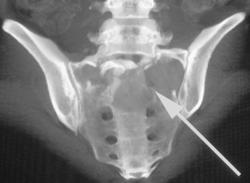

Diagnosis

CTA Axilla S/P Trauma With Nice Visualization of Axillary and Brachial Arteries